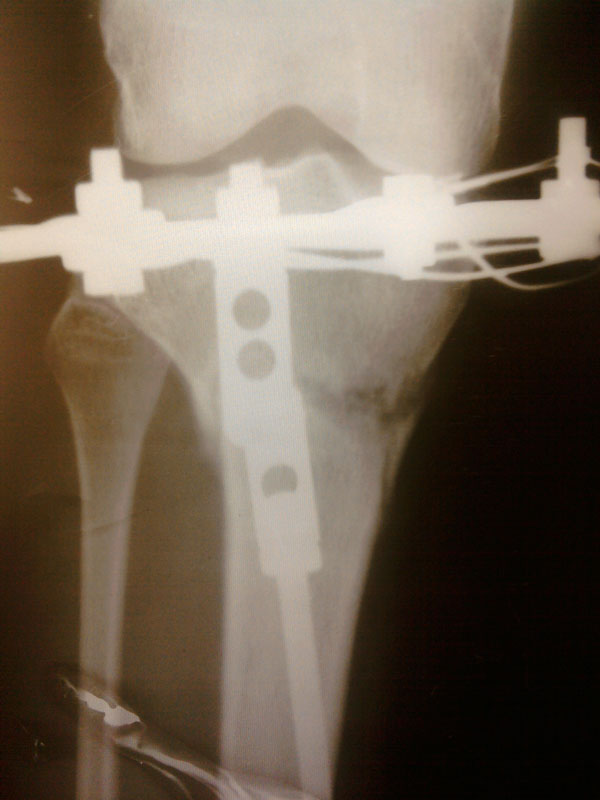

Здравствуйте, Николай Николаевич! Посмотрите мои снимки, пожалуйста - когда мне приезжать?

Здравствуйте, Марина! Судя по рентгеновским снимкам, регенерат(костная мозоль) у Вас замечательный. Чтобы не испытывать судьбу, учитывая всё таки выраженную деформацию ног, оптимальное снятие аппаратов(чтобы сразу ходить без костылей и других средств опоры) 20 марта. Осталось чуть- чуть потерпеть.

До встречи, удачи!